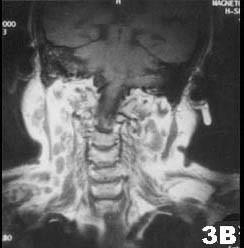

问题 肺结核患者发现双侧腮腺区肿块3个月,缓慢增大,无明显症状。查体腮腺区可触及局限性肿块,边界清,质软,可活动,轻压痛。CT 检查结果图示。首先考虑的诊断为 ( )

选项 A.腮腺囊肿 B.腮腺结核 C.慢性腮腺炎 D.腮腺腺样囊性癌 E.腮腺多形性腺瘤

答案 B